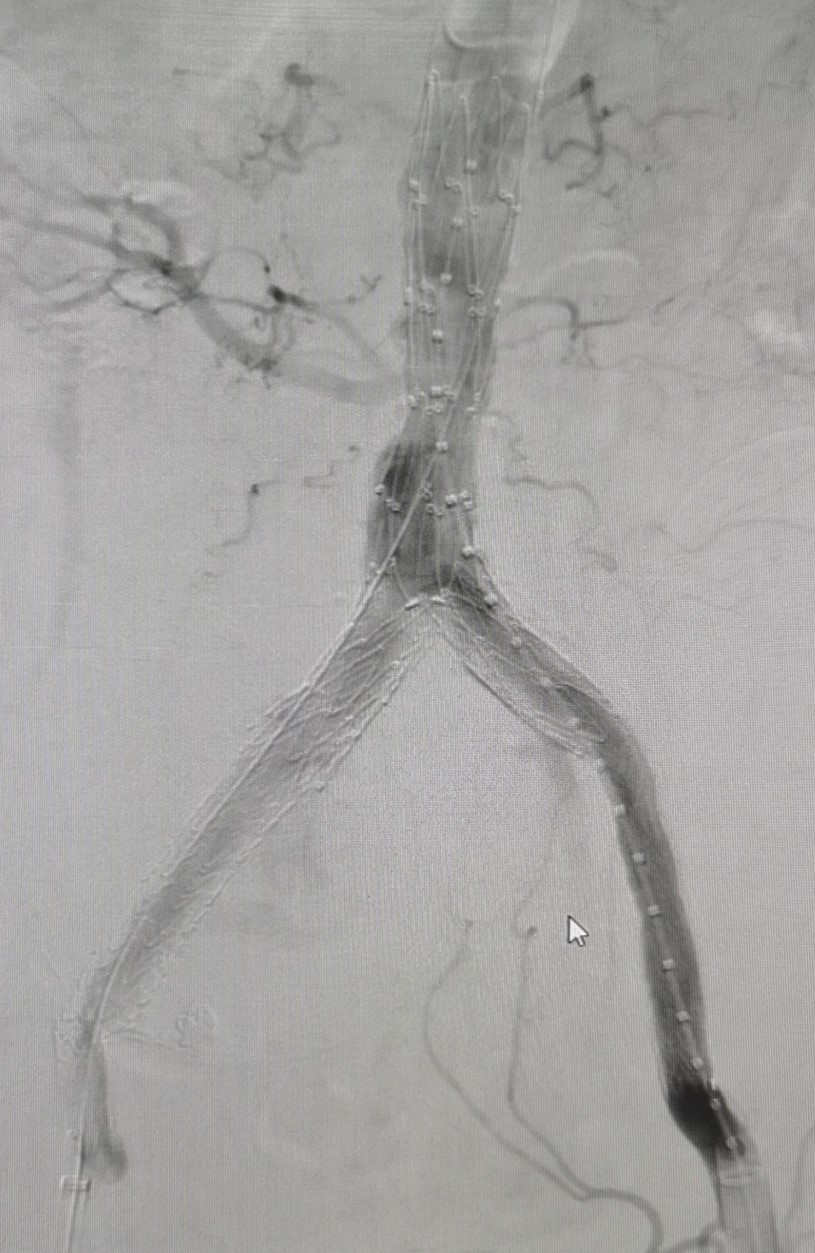

(左)腹主动脉支架置入前,(右)腹主动脉支架置入后

因患者为超高龄患者,且基础疾病多,血管病变中髂动脉瘤超大,胆囊巨大,两个病变都随时存在破馈风险,情况万分危急,患者命悬一线。急诊科迅速启动全院多学科大会诊,深夜共同讨论具体救治方案。副主任医师刘炼指出患者虽超高龄,但平时状态较好,且目前髂动脉瘤直径超过8cm,随时存在破溃风险,经逐级上报血管外科主任姚凯后,指示患者诊断明确,病情危重,需行急诊手术。经与患者及家属详细沟通并征得同意后,各学科通力合作,心内科、急诊科精准控制血压,麻醉手术科评估患者身体情况拟定麻醉方案,保障术中安全,超声科及影像科精确解析病变血管解剖结构及血管内病变性质,为血管腔内微创治疗提供有力支持,复合手术室极速完成行术前准备...微创手术腹主动脉、髂动脉覆膜支架腔内隔绝手术手术随即在周六的凌晨2时紧急开展,姚凯主任、王征副主任医师组成的专业血管疾病团队,克服患者超高龄、基础情况差等种种不利因素,成功克服全身多处血管钙化,主动脉狭窄、髂血管极度扭曲等困难,不到2小时就成功实施微创血管介入手术,术后患者平稳送入ICU病房。

中南大学湘雅三医院血管外科主任姚凯介绍主动脉瘤并非肿瘤,而是一种动脉扩张性疾病,是指由于动脉粥样硬化、炎症、感染、遗传等因素导致腹主动脉壁薄弱,在高压动脉血流作用下发生直径扩大,形成主动脉瘤样扩张,在动脉内血压的作用下局部吹气球般膨胀、变形至极限时会发生破裂。主、髂主动脉瘤是一种异常凶险的血管疾病,它像一个不定时炸弹,不知道什么时候就引起爆炸(即胸腹主动脉瘤破裂)。胸腹主动脉瘤破裂后死亡率极高,88%病人送达医院后2小时内死亡,其自然病程五年的存活率仅19.6%。此患者的巨大髂动脉瘤实属罕见,超过正常值5倍以上,就像气球濒临破溃的时刻。现微创血管介入腔内手术创伤小,时间短,为高龄的病危患者救治首选治疗方案。